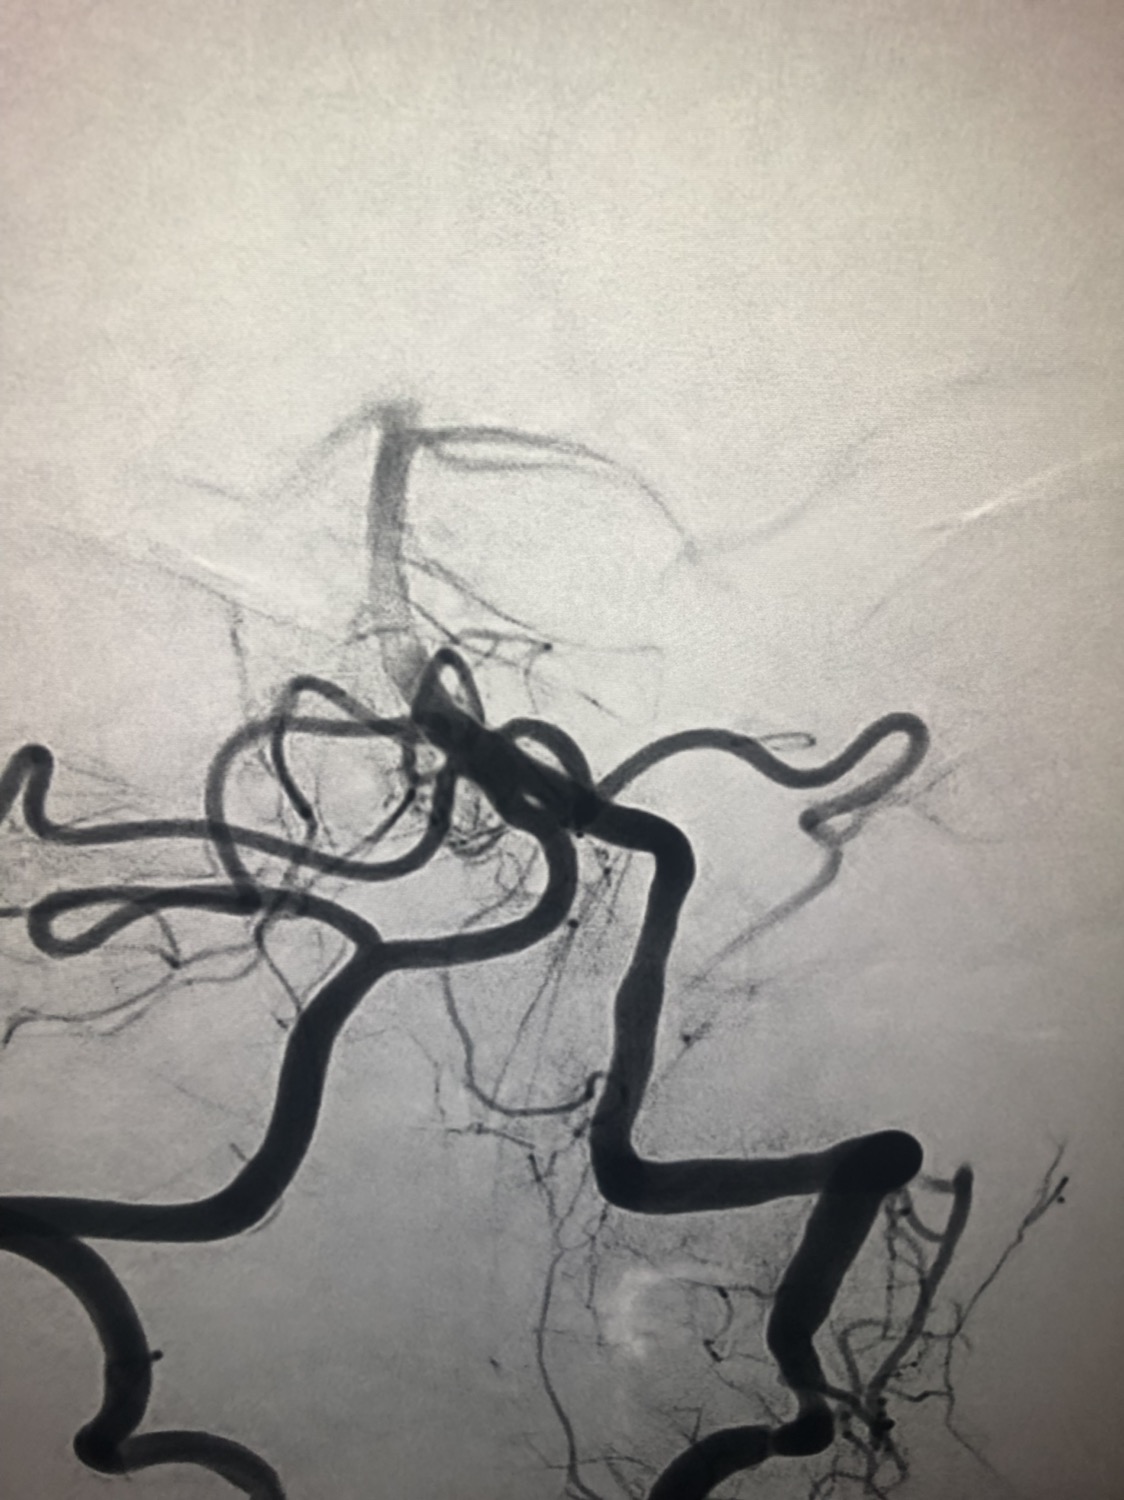

急诊二。zde,f53y。

意识模糊进行性加重8h,基底动脉闭塞,reco取栓再通,貌似动脉硬化,实际血管光滑。造影➕取栓8min。今日团队配合紧密,不到三小时全麻造影取栓带苏醒完成两台取栓。团队棒棒的!南阳市中心医院神经内科脑血管病介入团队

团队快速取栓:1.得益于医院领导打造的完备的绿色通道,快速检测。2.微信群转诊系统,提前在患者从基层转诊途中已经告知取栓团队病情。3.专门的一线医生负责带领急诊检查。4.专门的护理接诊团队,急诊抽血备皮尿管胃管快速到位。5.专门的麻醉团队,甚至比病人先到导管室,快速麻醉不到十分钟,精湛的麻醉技术。6.专门的取栓团队,各种完善的取栓技术及先进取栓器材。7.这两例支架打开后看到血栓感觉不太硬,血流部分恢复,没有等待5min直接取栓,都是一把取通。